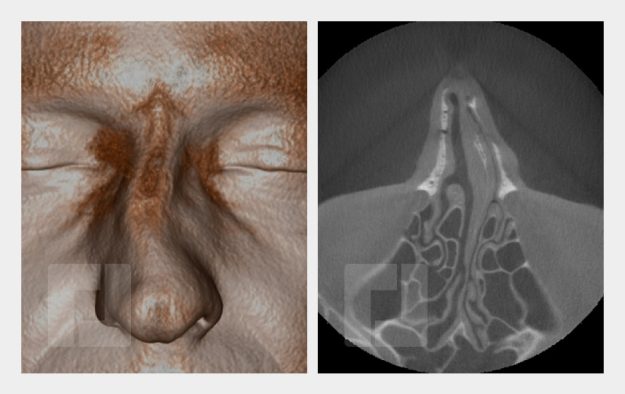

Beispiele

Durch Öffnen der Bildergalerie haben Sie die Möglichkeit selber durch die Beispiele zu navigieren.